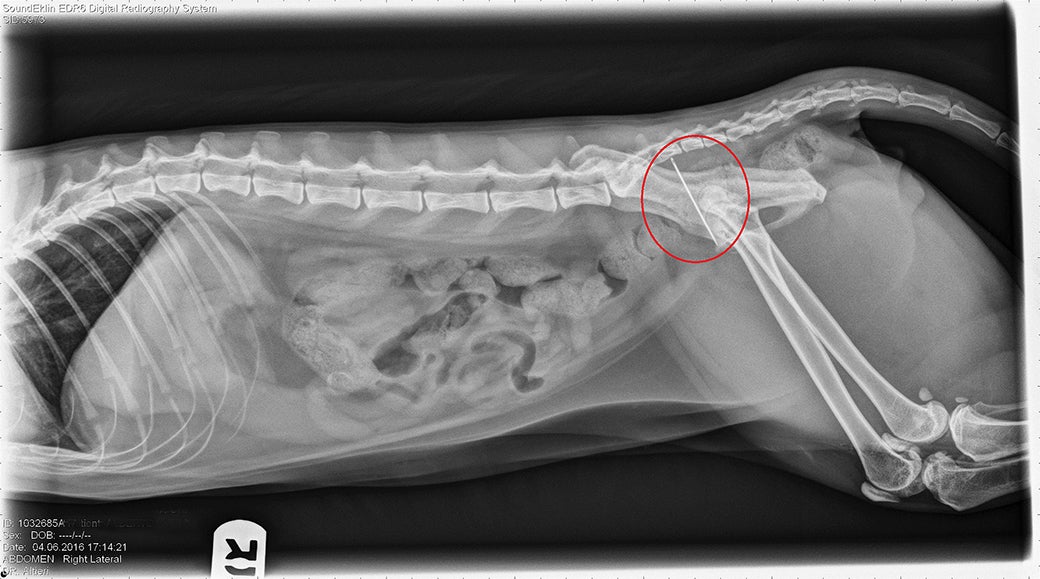

X Ray Shows Cat Swallowed Sewing Needle Aspca